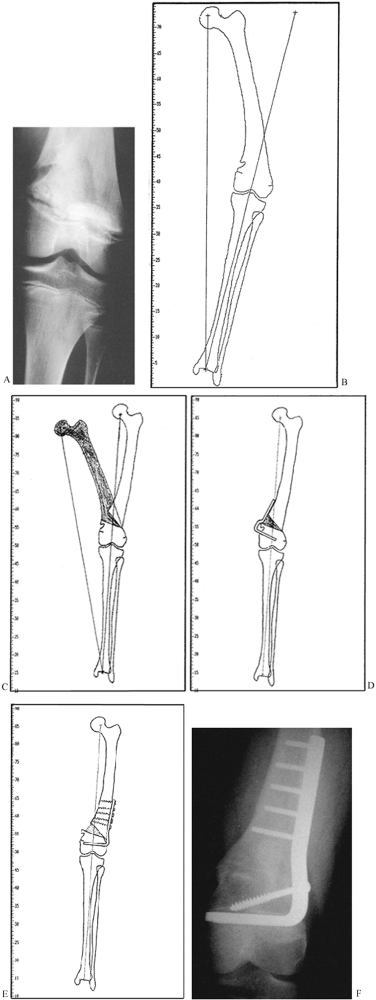

however. Take plain AP and lateral radiographs of both the affected and

the normal extremity, making certain that both are aligned with the

central beam of the x-ray. Use as long a tube distance as possible and

incorporate a radiographic ruler to assist in measurements. Either

include in those views the joints above and below, or take separate

views. In the lower extremity, determine the mechanical axis by taking

weight-bearing AP and lateral radiographs, using long cassettes to

include the hip and ankle joints. When trying to compare the axis of

the knee joint relative to the ankle joint, it is often helpful to take

independent AP films with the central beam at right angles, or with a

10° caudal tilt at the knee and AP at the ankle.